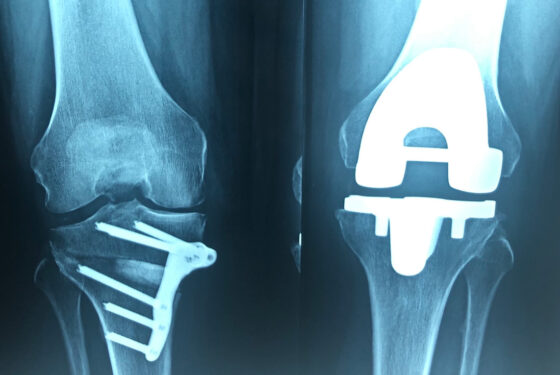

L’arthrose grave du genou grade 4 se traite habituellement par prothèse de genou. Depuis 2010, nous avons développé la chirurgie régénérative du cartilage dans l’arthrose grave du genou, chez le patient à bonne performance physique et encore jeune, par décompression de l’arthrose et thérapie cellulaire avec plaquettes sanguines concentrées.

​Nous continuons à mettre en place les prothèses de genou mais seulement aux patients âgés et à performance physique altérée.